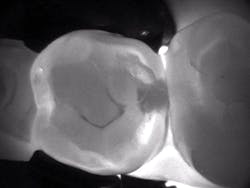

I have used several methods of caries detection, but as technology evolves, I am always looking for something better. My last device used numbers to calculate caries, but I found them to be inconsistent. I did not have a photo of the tooth to keep in the patient's record. Images from CariVu (DEXIS) look similar to a radiograph, so I can see for myself the dark areas that denote the presence of caries occlusally and interproximally, as well as cracks.

Now, rather than just treating caries, I can help to prevent its spread. In some instances, a smaller amount of decay would not be detected by digital x-rays. If the patient doesn't return for a couple of years, and I miss that early decay, it could easily lead to more invasive treatment. This is when my caries detector is most helpful. When patients see their own caries on the monitor, they are more apt to want me to take action sooner rather than later. They take ownership of their dental care because of this visual aid. After I open up the tooth, I can even use an intraoral camera to show the patient the decalcified or carious area. Even on small caries, CariVu is very predictable with a 99% accuracy rate.1

On the other hand, patients appreciate when my technology can actually lead me to wait instead of treating. In some cases, the CariVu images show a decalcified area that is not full-blown caries yet-that is, not fully into the dentin, but it is in the first stage of decay, even before it appears on a radiograph.2 With this type of incipient caries, sometimes I want to wait and monitor the area. It is interesting to note that after seeing the image, some patients will agree to wait. Others won't want to wait; they will ask me to move ahead with the restoration.

When an x-ray or visual exam shows what appears to be caries, but the CariVu image does not, I go with CariVu. For example, fracture lines can actually appear as dark-line caries but can also be severe staining. When I maneuver the tip in different angles, sometimes I can actually see this supposed "cavity" disappear. Patients appreciate when I can tell them that the area is not carious. Dentists are trusted, and I want to keep that trust. I don't want to drill a tooth that may not have decay. All dentists have seen what we thought was a cavity on an x-ray, drilled the tooth, and then thought, "Where's the cavity?" That is an uncomfortable situation that I can now avoid.